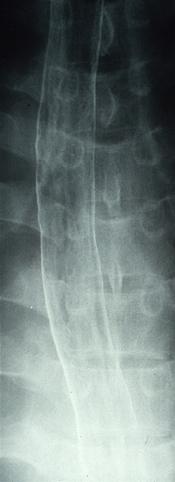

질환(병리주체)의 분류 악성 상피성종양/편평상피암

부위(장기별) 식도/중

검사방법 X-P

종양의 육안분류 0형(표재형)/I형(Isp)

종양의 최대경(밀리미터) 15~19

종양의 심달도 sm